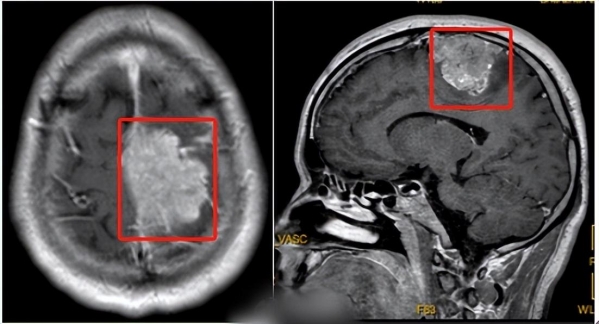

王先生意识到不对劲,立马前往医院检查,结果头颅磁共振检查显示左侧顶部颅内脑外实性肿块。王先生的脑袋里长了个矢状窦旁脑膜瘤,直径达到5.6cm。走路鞋子会掉就是因为压迫到神经,导致肢体偏瘫。